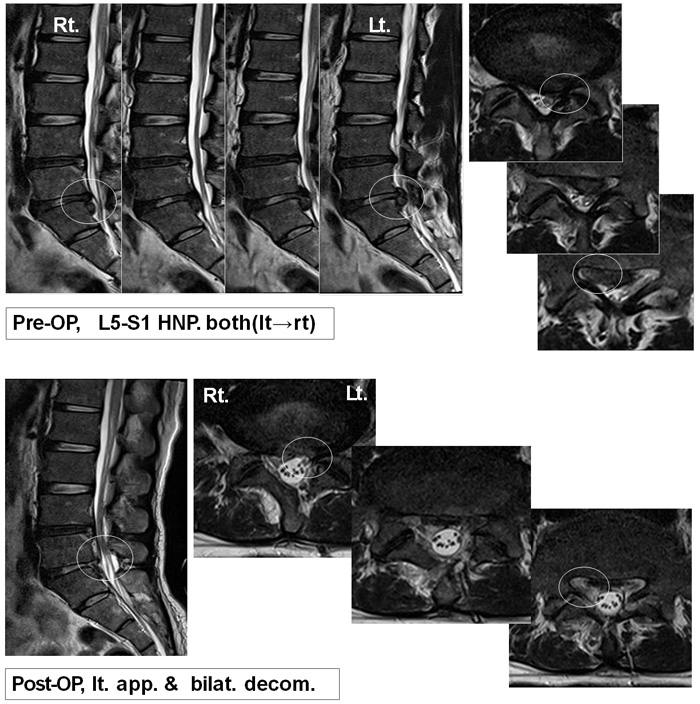

● 2포트 내시경적 척추시술(BESS) 허리에 약 5mm정도의 하나의 포트(경로)을 통하여 내시경을 삽입하여 병의 원인을 정확하게 봅니다. 다른 포트(경로)로 수술 기구를 삽입하여 척추질환의 원인인 비후된 인대나 뼈만을 확실하게 제거하는 최첨단 수술법입니다. 기존의 척추 내시경이 하나의 채널을 통해 보면서 동시에 수술을 해야 하므로 제한점이 많았지만, 2포트내시경수술은 두 개의 포트(경로)를 모두 이용하여 광범위하고 빠른 치료가 가능합니다. 따라서 기존의 신경성형술, 풍선확장술, 고주파디스크 성형술 등의 일반적인 시술에서 불가능 했던 근원적인 치료가 가능한 첨단 치료법입니다. ![]() ● 장점 - 흉터가 거의 생기지 않습니다. (5mm 2개) - 척추 불안정과 같은 후유증이 드뭅니다. - 수혈할 필요가 없습니다. - 신경 경막외 출혈이나 신경 주위의 유착이 적습니다. - 입원 기간이 짧아(약 2박3일) 일상 생활 복귀가 빠릅니다. (1~2주) - 치료 후 재활이 필요 없습니다. 추후 운동 및 자세 관리는 필요합니다. - 전신마취가 필요 없습니다. ![]() ● 대상 - 각종 치료에 효과가 적었던 심한 척추관협착증 환자 - 중증도 이상의 심한 추간판탈출증 환자 - 고령자나 만성 질환으로 수술이 힘든 환자 - 전신마취 혹은 수술이 두려운 환자 - 조기 회복이 필요한 환자 ![]()